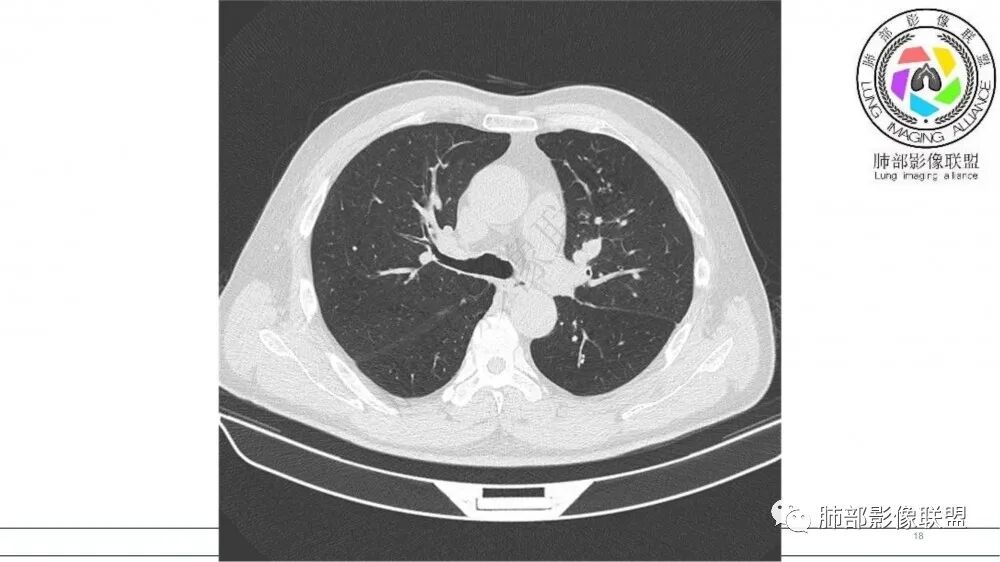

左肺上叶前段支气管内铸形生长软组织影,增强后均匀强化,远侧见斑片状磨玻璃影。考虑恶性病变,粘表?粘液腺?

老年男性,左肺上叶前段支气管内铸形阴影,增强后病灶不均匀强化,内部有坏死?远端可见斑片状阴影(阻塞性肺炎)。考虑恶性病变,老年人,鳞?类癌?粘表不能排除。

左肺上叶前段支气管杵状指样扩张,内见实性组织阻塞性,并强化明显,边缘饱满,周边多发小斑点影,小花小草征,老年男性,长期吸烟史,方向恶性,首选支气管内浸润鳞Ca可能性大。

男,70岁,吸烟史,咳嗽,胸闷憋气一个月,左肺上叶不规则形软组织密度影,病灶沿支气管走形,周围见粟粒及棉絮样稍高密度影,增强扫描病灶内见少许坏死,考虑鳞癌可能,鉴别结核。

老年男性,肺气肿,吸烟史,左肺上支气管腔内铸型高密度影,呈指套状,远端多发树芽,增强不均匀强化,考虑鳞癌,鉴别小细胞癌

B3指套征,常规不是鳞癌就是ABPA,有强化丶血管造影征,倾向于鳞癌

老年男性,长期吸烟史。左上肺前段沿支气管走形的指套样病变,增强可见病灶强化(排除结核、ABPA(也无气喘症状)),远端多发点状高密度影。考虑恶性肿瘤,鳞癌可能性大。

指套征,扩张支气管内软组织强化,远侧肺野阻塞性炎,纵隔、左肺门肿大淋巴结;老年男性,吸烟,考虑鳞癌,鉴别小

指套征:是影像征象,胸部平片表现为手指状密度增高影,以肺门为中心呈放射状分布,CT显示扩张支气管内低密度黏液栓形成或实性病变,呈管状、树枝状或卵圆形密度增高影;支气管扩张伴近端梗阻时,扩张支气管内部黏液分泌物不能排出而形成。可以伴随远端空气潴留征、阻塞性炎症。